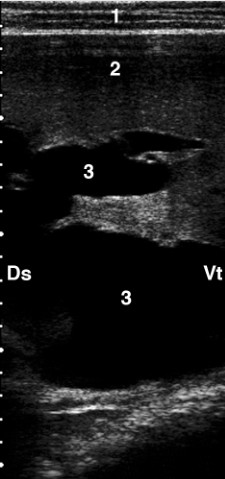

正常牛胆囊超声图

胆管钙化***常见的原因是慢性片形吸虫病。 钙化胆管导致肝实质中离散的超声变化。 它们具有强烈的高回声并伴有远端声影。 在横截面中,钙化胆管呈环状(看下图),在纵切面中,钙化胆管呈管状高回声结构。

胆囊在肝脏腹内侧成像,并与颅十二指肠密切相关,它表现为黑色囊肿(充满液体的囊泡),管腔无回声,边缘有细小的回声,呈梨形。胆囊管在纵向截面上成像为细长的无回声结构,具有回声壁,在横截面上成像为管状无回声结构,在截面上具有回声壁(看下图)。